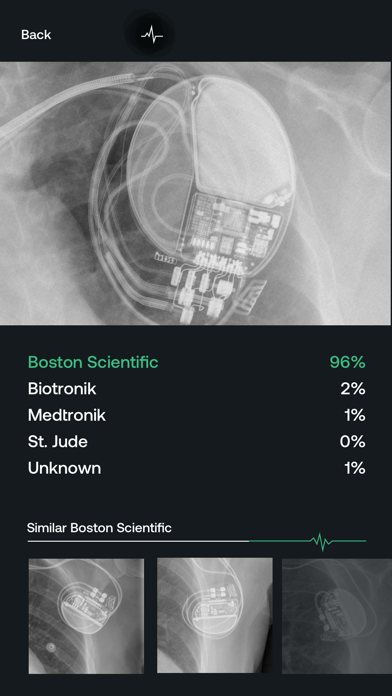

Pacemaker-ID uses a deep-learning model to determine the manufacturer of a given pacemaker and defibrillator in an x-ray image.

Currently, we support detection of:

- Boston Scientific

- Biotronik

- Medtronic

- St. Jude